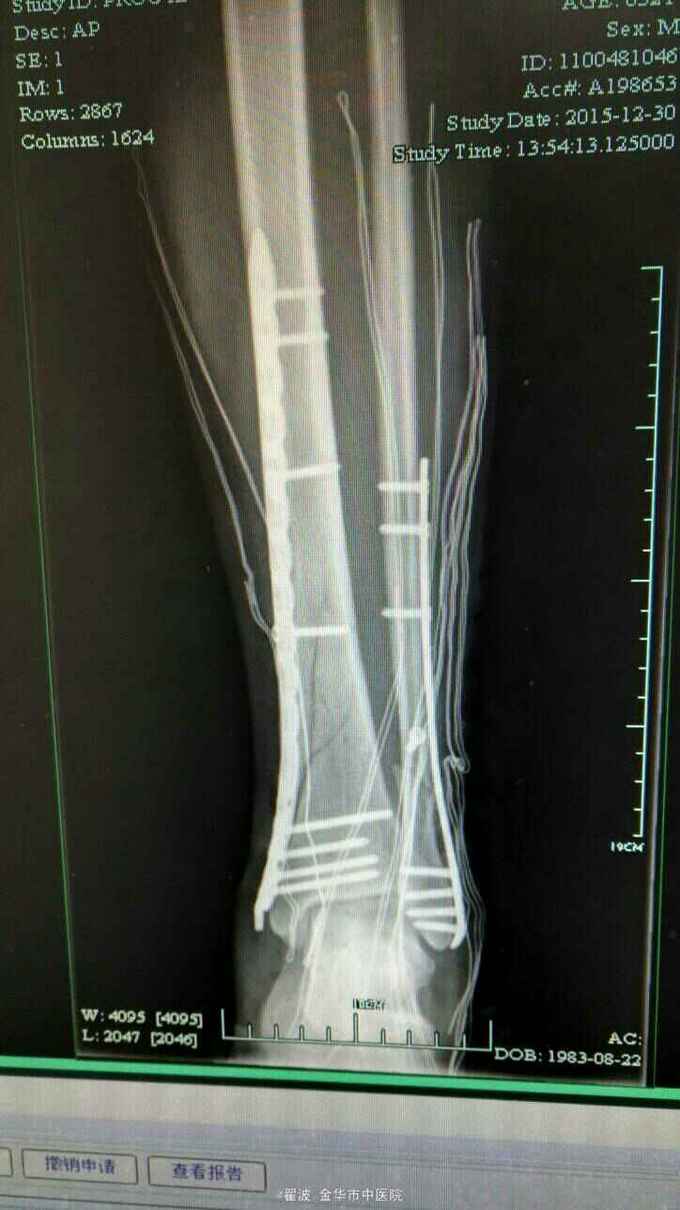

伤后肿胀很明显,可见张力性水泡,出现皱褶才手术。